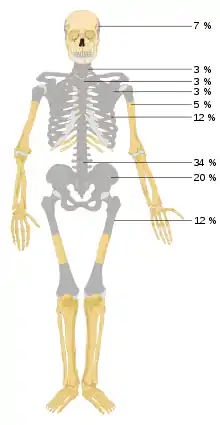

Les métastases osseuses sont largement plus fréquentes que les tumeurs osseuses primitives, comme l'ostéosarcome. Aux États-Unis, on compte environ 1,3 million de nouveaux cas de cancer par an. Environ 50 % d'entre eux développent des métastases osseuses, ce que l'on peut démontrer aussi par les temps de vie. Face à cela, on compte environ 2000 cas de tumeurs primitives des os[8]p. 506. Sur l’exemple de l’ostéosarcome, la plus courante des tumeurs malignes des os, il y a en Allemagne environ 200 nouveaux cas par an. Face à cela, on trouve dans une autopsie soigneuse, des métastases osseuses chez environ 70 % des patients qui meurent de cancer[9],[10],[11],[12].

La probabilité d'une métastase osseuse dépend fortement de la tumeur primitive et de son stade. Chez les hommes décédés de Cancer de la prostate, par exemple, on peut trouver chez 90 % d'entre eux des métastases osseuses[19],[20]. Pour le cancer du sein, les métastases osseuses sont extrêmement fréquentes. 90 % de toutes les métastases osseuses proviennent de cancers du sein, de la prostate, des bronches, des reins ou de myélome multiple[3]. Les métastases osseuses sont rares pour les sarcomes ou pour les lymphomes – à part le myélome multiple cité ci-dessus[21].

Les métastases osseuses apparaissent dans environ 75 % des cas à plusieurs. Dans les autres cas, elles sont solitaires, et peuvent simuler une tumeur osseuse primitive[1].